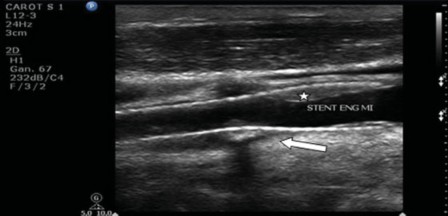

En modo B se obtiene "información morfológica." Ecográficamente el stent es hiperecogénico y puede estar posicionado desde la arteria carótida común en su porción distal o en el nacimiento inmediato de la ACI, con longitudes variables. Es importante registrar la morfología correcta de las paredes de las arterias nativas adyacentes al stent y ver la existencia de placas subyacentes en la zona de estenosis, las cuales pueden provocar una deformidad de la pared del stent y, además, la existencia de placas no cubiertas por el stent. Se debe observar la integridad del mismo y evaluar posibles rupturas (►Fig. 4).

Ecografía en modo B donde se observa stent con buena posición y aposición a la pared vascular, sin anormalidades en su calibre y luz vascular residual (Flecha).

En caso de estenosis a causa de disección, el tratamiento puede requerir la colocación de dos stent y, por ende, es posible la existencia de desacoples.

En los implantes tipo Wallstent®, los más utilizados, cuentan con ciertas desventajas. Una de ellas es la falta de flexibilidad longitudinal, por lo que una vez expandido rectifica la arteria y puede provocar la formación de una angulación de la misma en el extremo distal del stent. Otra desventaja podría ser una mala adapatación a la silueta de la arteria que provoca la formación de espacios muertos entre el stent y la pared arterial por mala aposición, aunque es un hallazgo poco frecuente.9 Todos esos hallazgos deben ser observados y descriptos con el EDC.